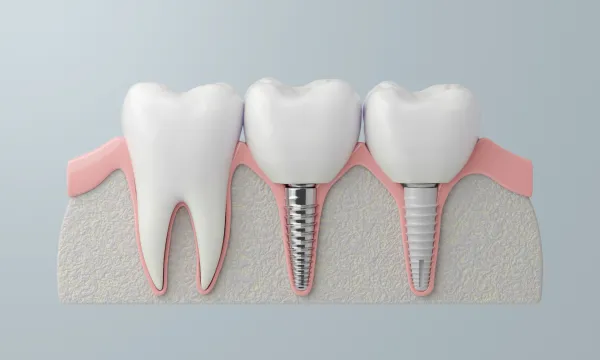

インプラントの場合

1本単位で骨に固定するため、隣の歯を傷つけずに天然歯に近い咬合力を回復できます。単独で機能するため安定性が高く、違和感も少ないのが特長です。

噛む刺激を直接骨に伝えるため、骨吸収を防ぎやすく、長期的な安定につながります。定期的なメンテナンスで機能性を維持できます。